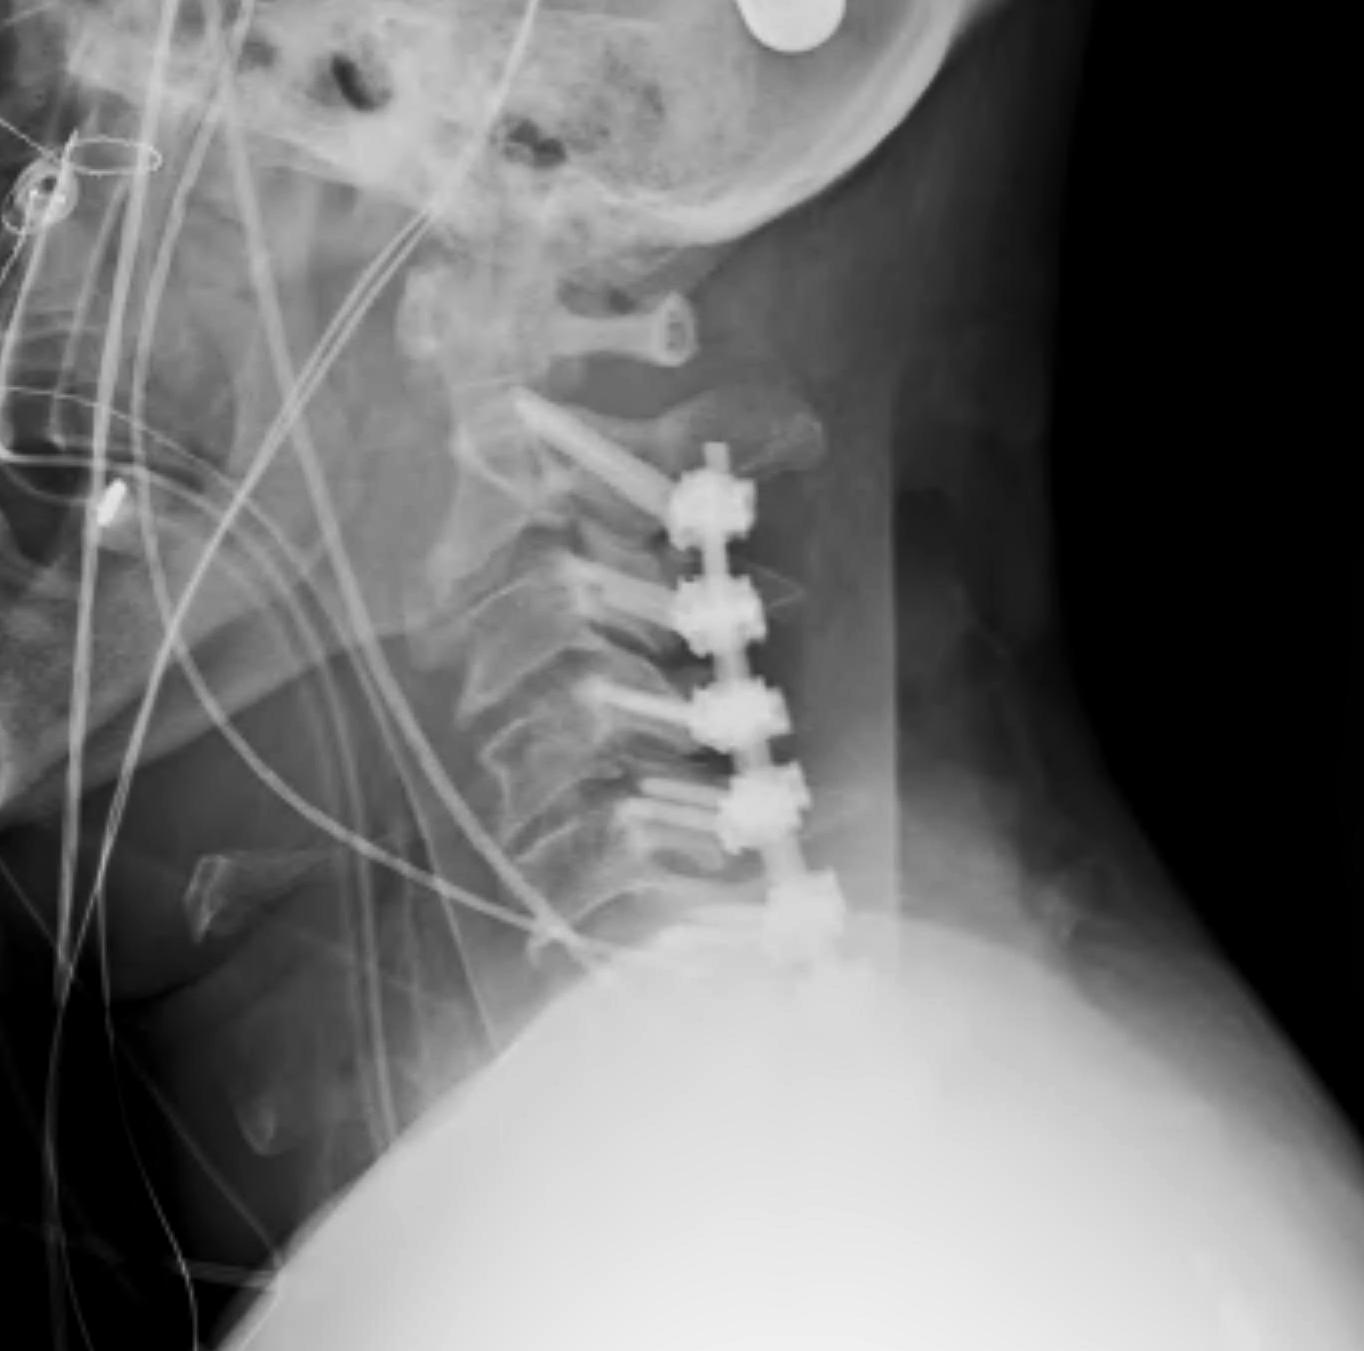

Posterior approach

Advantage

- easier to reduce as direct access to facets

- biomechanically stronger fixation

Disadvantage

- increased wound problems

- ? risk of increased neurology with herniated disc

Technique

- distraction manoeuvre

- instrument between pedicles to reduce

- posterior stabilization or anterior stabilization